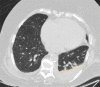

The coronavirus disease 2019 (COVID-19) pandemic is a global health care emergency. Although reverse-transcription polymerase chain reaction testing is the reference standard method to identify patients with COVID-19 infection, chest radiography and CT play a vital role in the detection and management of these patients. Prediction models for COVID-19 imaging are rapidly being developed to support medical decision making. However, inadequate availability of a diverse annotated data set has limited the performance and generalizability of existing models. To address this unmet need, the RSNA and Society of Thoracic Radiology collaborated to develop the RSNA International COVID-19 Open Radiology Database (RICORD). This database is the first multi-institutional, multinational, expert-annotated COVID-19 imaging data set. It is made freely available to the machine learning community as a research and educational resource for COVID-19 chest imaging. Pixel-level volumetric segmentation with clinical annotations was performed by thoracic radiology subspecialists for all COVID-19-positive thoracic CT scans. The labeling schema was coordinated with other international consensus panels and COVID-19 data annotation efforts, the European Society of Medical Imaging Informatics, the American College of Radiology, and the American Association of Physicists in Medicine. Study-level COVID-19 classification labels for chest radiographs were annotated by three radiologists, with majority vote adjudication by board-certified radiologists. RICORD consists of 240 thoracic CT scans and 1000 chest radiographs contributed from four international sites. It is anticipated that RICORD will ideally lead to prediction models that can demonstrate sustained performance across populations and health care systems.